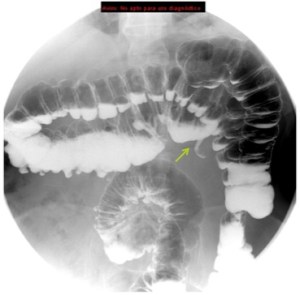

Se revisarón estudio previos, en un enema baritado y TC se observó:

Enema baritado con ciego (con apéndice visible) en posición anómala, localizado en hipocondrio izquierdo. TAC de adomen con signo de remolino o Twister de vasos. Otro hallazgo sería encontrar la VMS a la izquierda de la AMS.

Diagnóstico: MALROTACIÓN INTESTINAL.